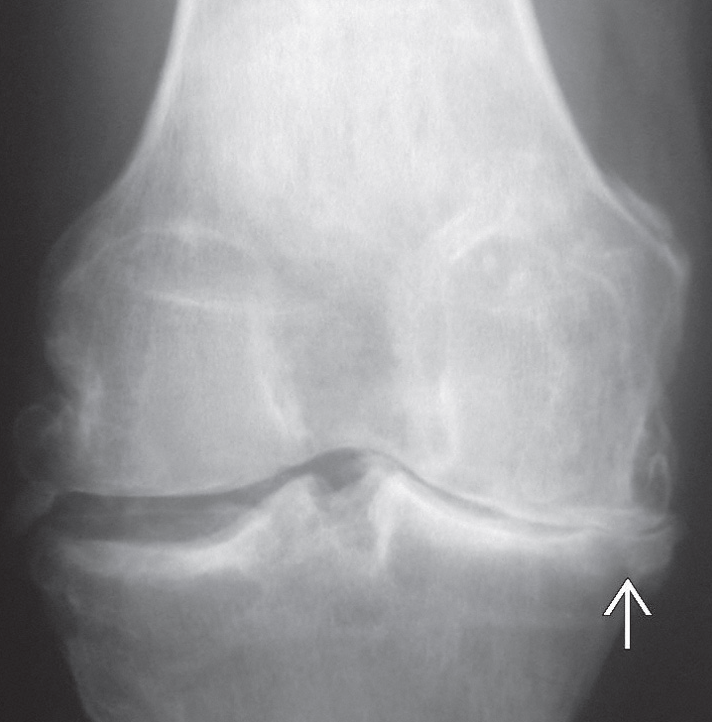

Röntgen ile eklem aralığında daralma, kemikteki değişiklikler ve kemik çıkıntılarının (osteofit) oluşumu tespit edilir.

Diz ekleminin iç bölümünde artroz bulguları. Eklem aralığı daralmış.